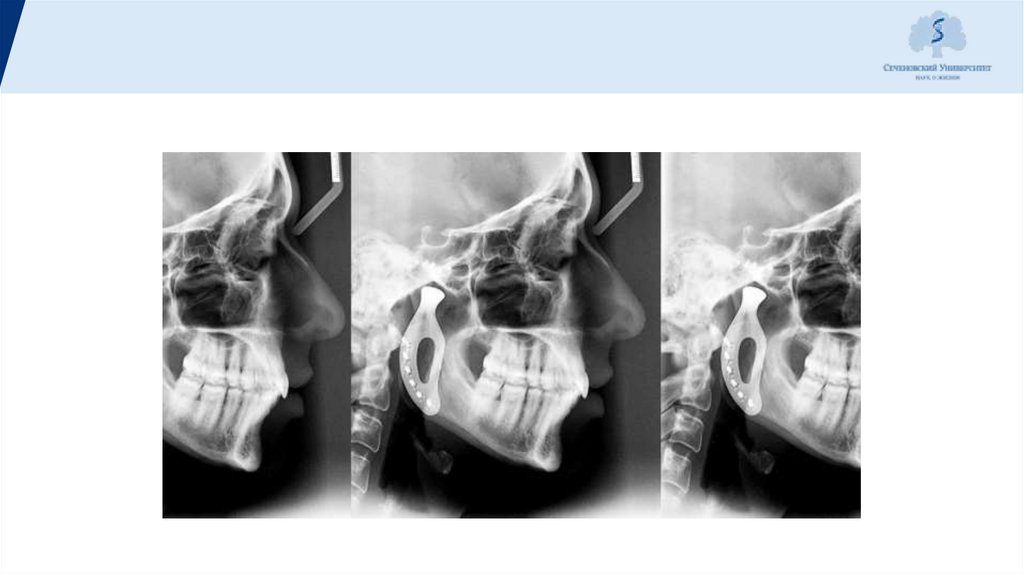

Томограммы правого и

левого ВНЧС.

Диагноз:

правосторонний

нейромускулярный

дисфункциональный

синдром ВНЧС